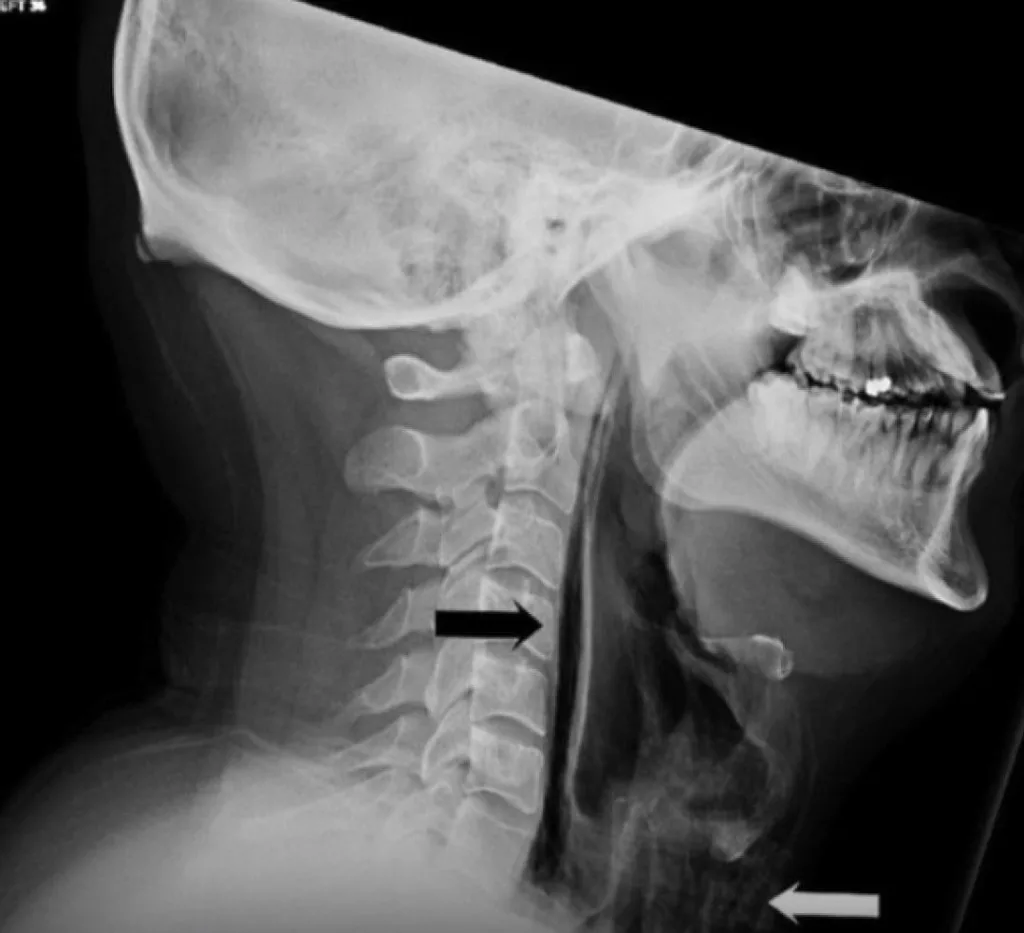

Рентген показал серьёзные повреждения — разрыв глотки, а в области шеи скопился воздух перед трахеей. Врачи предупредили, что помимо травм глотки, возможен разрыв барабанной перепонки или даже аневризмы головного мозга.